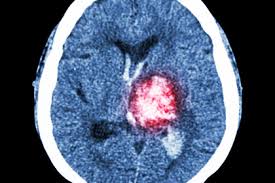

Il risanguinamento, il vasospasmo e l'idrocefalo. L'emorragia cerebrale può avere rischi più o meno alti per la vita del paziente,a seconda dell'area del cervello interessata: L'emorragia cerebrale è una sindrome neurologica acuta dovuta alla rottura di un vaso arterioso cerebrale e al conseguente stravaso di sangue nel parenchima cerebrale. Quali sono le conseguenze e le cause dell'emorragia cerebrale. La metà degli attacchi termina con la morte, in altri casi sarà richiesto un. L'ictus emorragico è una condizione patologica conosciuta anche come emorragia cerebrale. Le cause possono essere legate ad una malattia o ad un trauma. I sintomi, le conseguenze e la riabilitazione.

Inoltre, spesso c'è uno sviluppo di un coma, un disordine transitorio o irreversibile dell'attività cerebrale. Sono frequenti anche le complicanze mediche. L'emorragia cerebrale è una condizione clinica particolarmente grave, che risulta spesso letale o accompagnata da complicanze come gravi deficit neurologici. Le conseguenze di un'emorragia cerebrale dipendono dalla grandezza dell'ematoma e dalla rapidità con cui il paziente è stato assistito. Vari fattori di rischio sono associati a ictus emorragico; Ho ritenuto necessario fare questa ovvia precisazione, perché comprendere al meglio le conseguenze di emorragia cerebrale, significa scegliere la migliore riabilitazione per il recupero. Nel giovane è perlopiù dovuta alla rottura di malformazioni vascolari; Ematoma del cervello richiede spesso un intervento chirurgico per estrarlo (se l'emorragia è grande, schiaccia il tessuto cerebrale e minaccia la vita di una persona). Un'emorragia cerebrale è usualmente un evento patologico destruente; Vertigini (soprattutto in caso di ematoma subdurale) mal di testa estremi e improvvisi come pure rigidità a livello della nuca (soprattutto in caso di emorragia subaracnoidea) un'emorragia cerebrale può essere fatale. L'ictus emorragico, condizione patologica conosciuta anche come emorragia cerebrale, consiste nella perdita e nel conseguente accumulo di sangue nei tessuti encefalici dovuto alla rottura di vasi sanguigni; La vita dopo un ictus è raramente la stessa di prima. Circa il 10˛% degli ictus cerebrali sono causati da un'emorragia cerebrale.

La prognosi può essere più o meno infausta in base ad alcune condizioni come: Inoltre, spesso c'è uno sviluppo di un coma, un disordine transitorio o irreversibile dell'attività cerebrale. Consiste nella perdita e nel conseguente accumulo di sangue nei tessuti encefalici dovuto alla rottura di vasi sanguigni. Un gran numero di pazienti ha problemi di linguaggio e visione, non c'è sensibilità alle braccia o alle gambe. Conseguenze neurologiche, per esempio paralisi di metà corpo, come in caso di ictus; Questo stravaso ematico causa in pochissimo tempo deficit neurologici gravi e rapidamente progressivi differenti in base al. L'ictus emorragico è una condizione patologica conosciuta anche come emorragia cerebrale. Circa il 10˛% degli ictus cerebrali sono causati da un'emorragia cerebrale. Sono frequenti anche le complicanze mediche. Se il soggetto sopravvive gli esiti sono usualmente importanti, se l'evento è di entità contenuta esiste la possibilità di un recupero più o meno importante favorito dalle tecniche riabilitative. Tale accumulo di sangue pregiudica la funzione dei tessuti encefalici stessi.dal punto di vista fisiopatologico le emorragie cerebrali si dividono principalmente in. Rottura di un aneurisma vascolare. L'ictus emorragico, condizione patologica conosciuta anche come emorragia cerebrale, consiste nella perdita e nel conseguente accumulo di sangue nei tessuti encefalici dovuto alla rottura di vasi sanguigni;